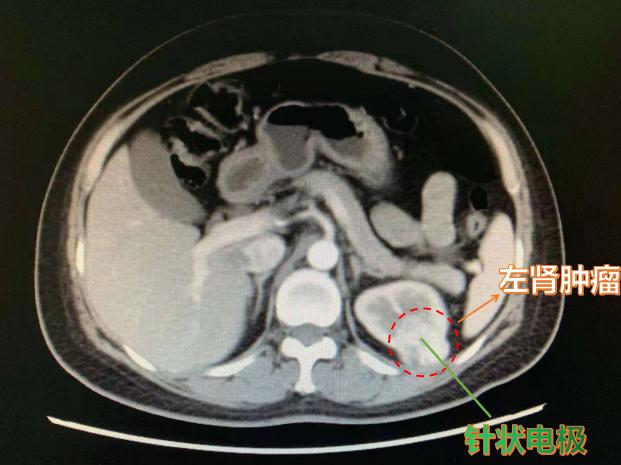

晚期肾癌的热消融主要包括射频消融、微波消融、激光消融、高能聚焦超声等方式。其原理是通过将针状电极等插入肿瘤组织内,在持续的电流/微波/激光/超声的作用下,局部产生60-100℃高温,导致肿瘤细胞发生蛋白质变性、坏死,同时使得供应肿瘤的血管发生闭塞,达到减少肿瘤组织供血、降低肿瘤细胞通过血液扩散的目的。